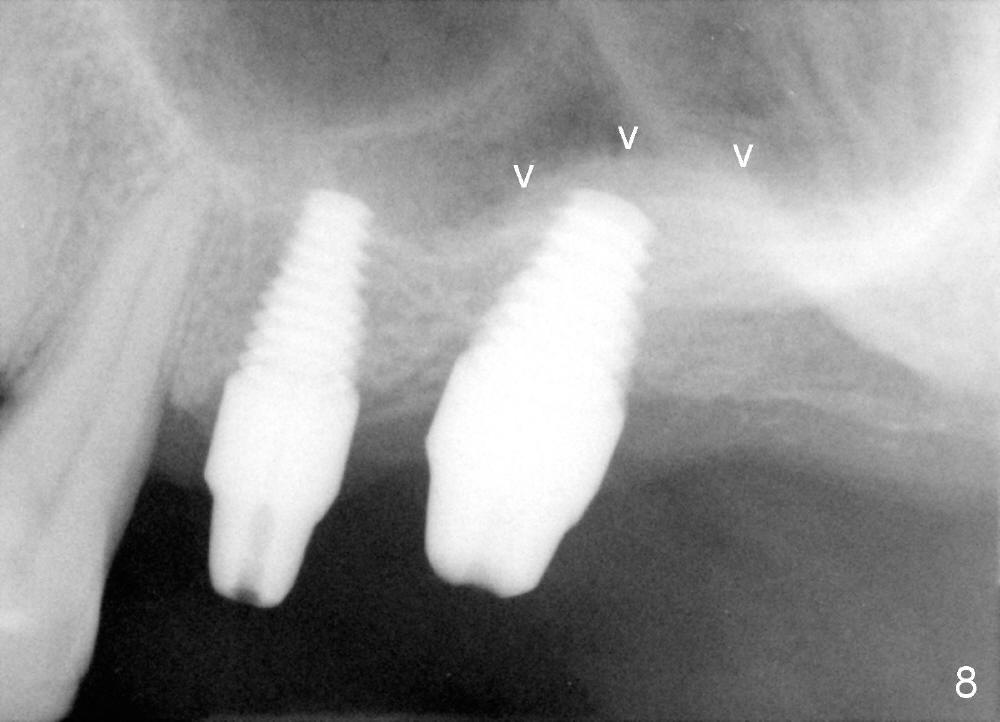

Bone graft remains in place 2 months postop (Fig.7 arrowheads); its density increses 4 months postop (Fig.8). The gingiva around the implant and abutment at the site of #14 is healthy (Fig.9 (4 months postop before final impression);10 (5 months postop immediately before final cementation)).